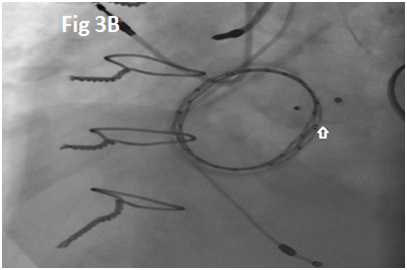

A 73-year-old female with mechanical mitral valve, tricuspid annuloplasty (32mm Edwards Physio Tricuspid incomplete ring) underwent Transcatheter Tricuspid Valve Replacement (TTVR) using off-label 29mm Edwards Sapien 3 (S3) Transcatheter Heart Valve (THV). Immediate post valve deployment, mild Perivalvular Leak (PVL) was noticed at the septal aspect (area of incomplete annuloplasty ring). Eighteen months later, patient presented with recurrent right heart failure and paracentesis due to severe tricuspid PVL (Figure 1A-C, Video 1). Percutaneous PVL closure under general anesthesia, Trans-esophageal Echocardiography (TEE) was performed. Via femoral venous access, defect was easily crossed with Agilis steerable sheath, multipurpose catheter and 0.035” glide wire. Despite recurrent attempts, wire came through the PVL but then traversed through open cells of S3 into the right ventricle (Figure 2A), confirmed with Armada 6mm balloon waist at the S3 cage (Figure 2B) (despite inflating 28mm Z med balloon inside S3 cage, Figure 2C). We decided to partially deploy the plug and assess valve function. Using 7.5F Asahi Eaucath multipurpose guide, a 12mm AmplatzerTM Vascular plug II (AVP II) was advanced through the defect. The ventricular disc was opened inside the S3 cage while body in the PVL defect (outside the S3 cage) and atrial disc on the atrial side of PVL (Figure 3A-B). With S3 function unaffected, no central leak and minimal gradient, PVL reduced to mild severity (Figure 4A-D, Video 2); the AVP II was successfully deployed (Figure 5). At 3-month follow up, there was an excellent symptomatic improvement (NYHA functional class I), with no heart failure re-hospitalization or paracentesis. Deployment of plug disc inside the valve frame is not recommended due to fear of interference with leaflet function and possible injury in long term. There was no immediate issue with the valve function in this case (due to space between the leaflet and frame of S3 and depends on size of plug used). Valve-in-Valve (S3-in-S3) would have certainly sealed all open cells treating this PVL but is more expensive option.

Figure 1 Para-valvular leak shown by color Doppler (1A) on 2D and 3D (1B) images, along with dense tricuspid spectral Doppler signal with peak velocity of 3m/s (1C).